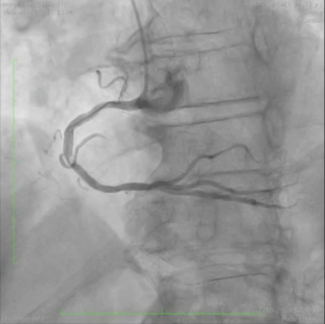

Andrea Ascione, MD; Alessio Arrivi, MD, PhD, FESC; Marcello Dominici, MD; Nicola Bier, MD

To our knowledge, this is the longest coronary thrombus ever reported to be removed in its entirety.